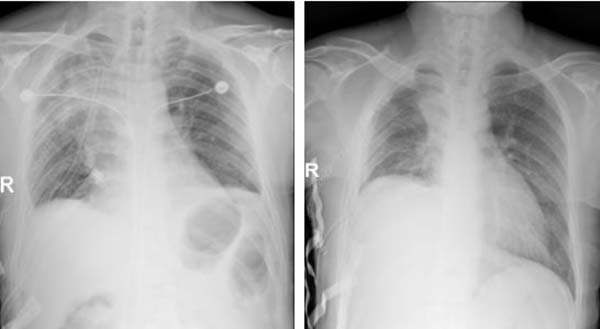

左:患者董xx 术后查房床旁胸片

右:患者孙xx 术后复查床旁胸片